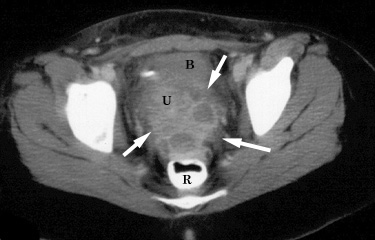

КТ-исследование абсцесса малого таза: Визуализация и диагностика

Раздел: Фотоальбом решений